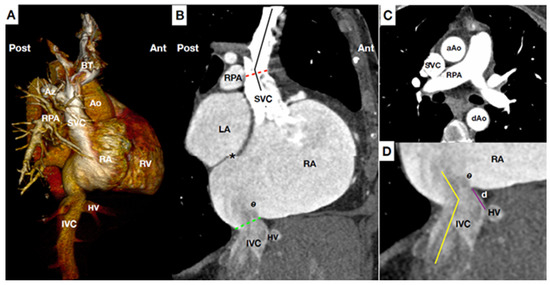

2.2. CAVI: Anatomical Considerations